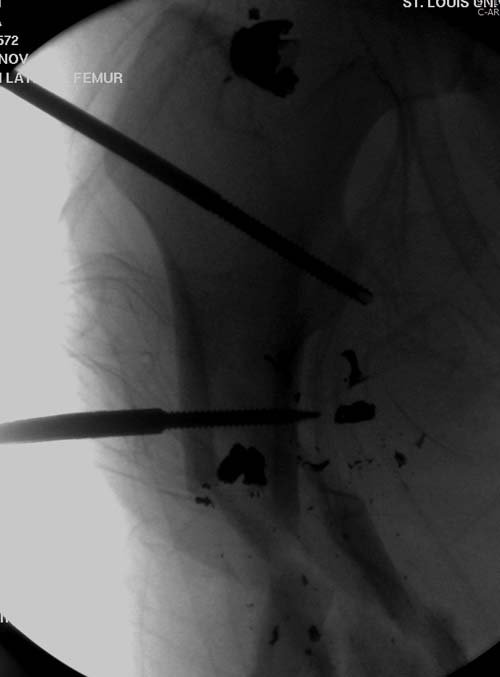

Беспокойство проявил недавно, по поводу жалоб на боли сделано МРТ и

дренирование абсцесса терапевтами. Мы удалили гвоздь, сделали I&D,

рассверливание канала, и ввели гвоздь с антибиотиком. Для гвоздя

использовали стерильную трубку-форму, а антибиотик по 1.0 Tobramycin c

Vancomycin.

В замкнутом без перелома пространстве во время риминга повышается

давление внутри канала, и имеется риск тромбообразования. Для

профилактики и для дренажа - канюлированный винт 6.5 мм в дистальной

части бедра. Обработку заканчивают культурой из раны и канала. Иногда